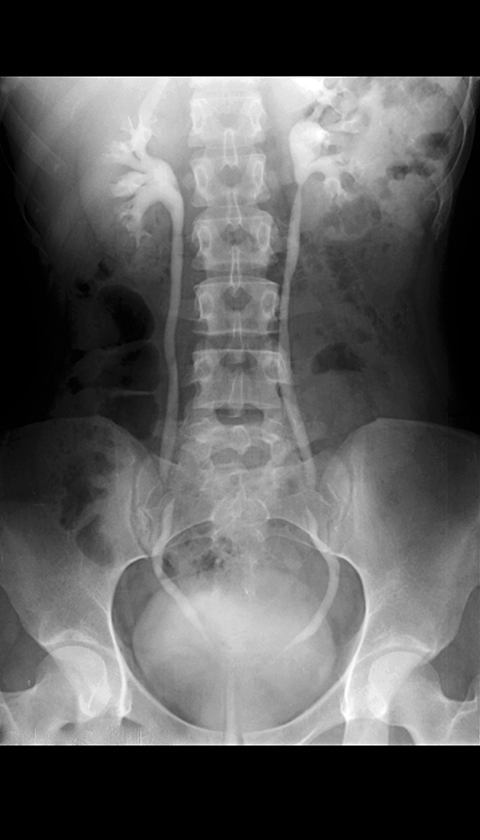

Excretory Urogram